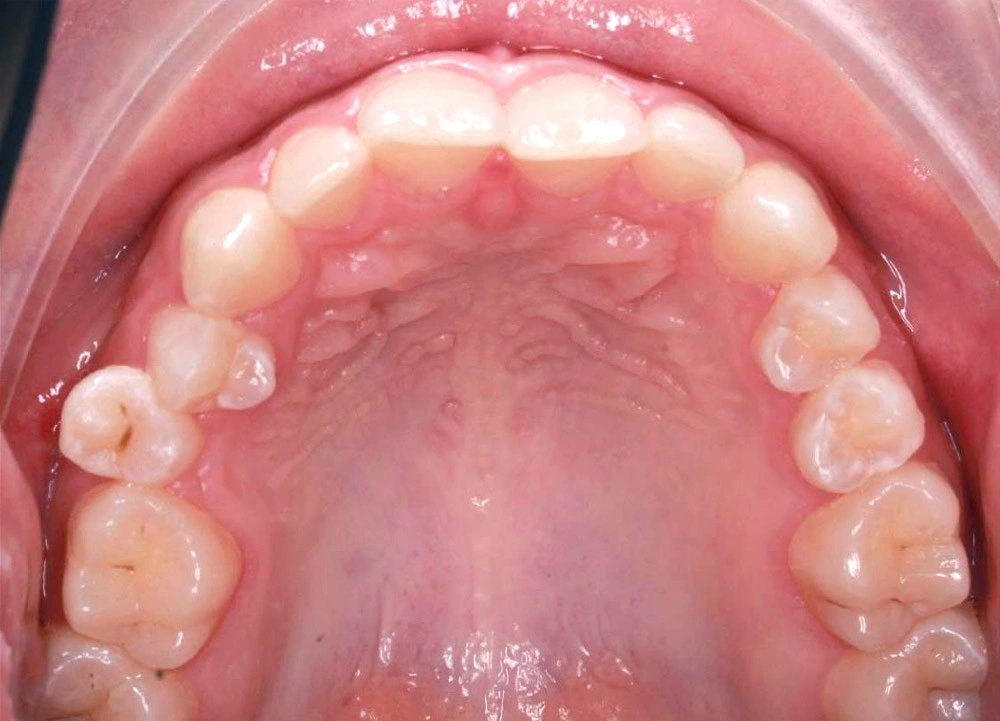

Глубокий прикус - Кейс 5

Эффективность устранения дефекта прикуса посредством элайнеров FlexiLigner.

16

Количество кап НЧ

Количество кап ВЧ

Результаты лечения